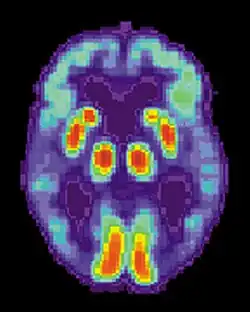

PET scan of a healthy brain - Image courtesy of US National Institute on Aging Alzheimer's Disease Education and Referral Center -

PET scan of brain with AD - Image courtesy of US National Institute on Aging Alzheimer's Disease Education and Referral Center